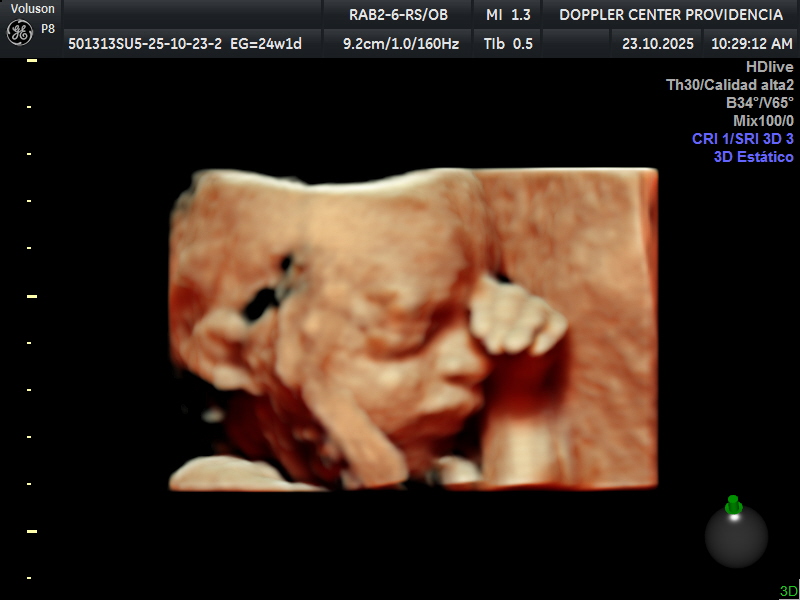

• Eco Doppler 22-24 semanas

Doppler Center